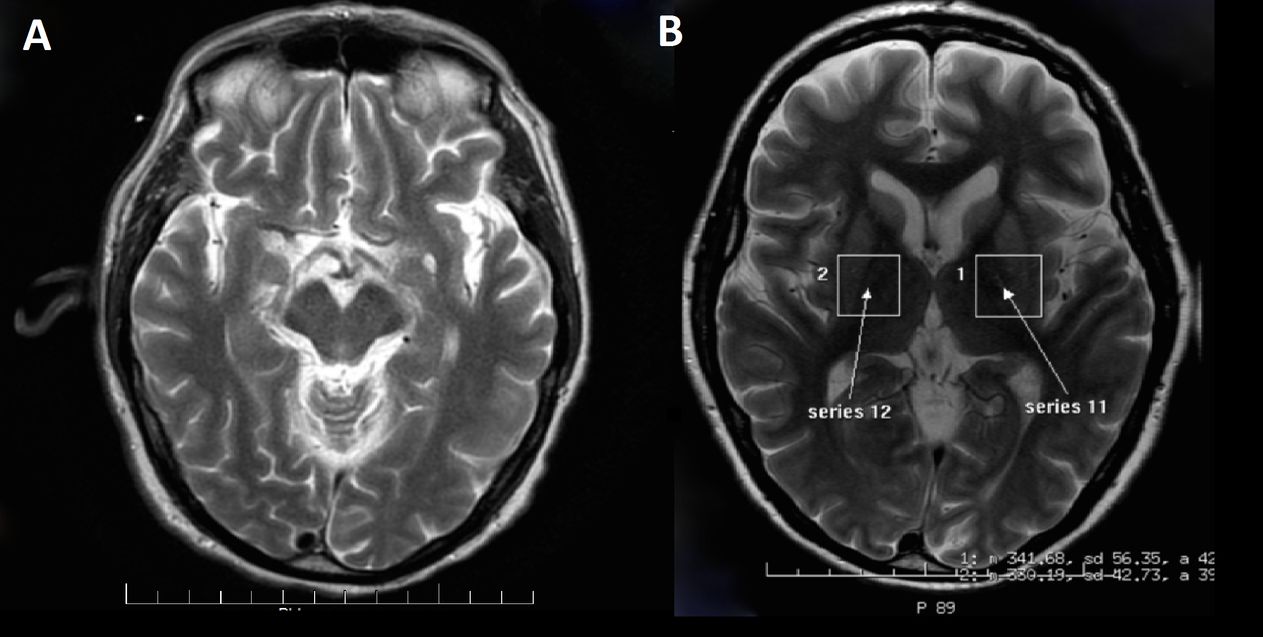

Some tests, such as brain magnetic resonance imaging and electroencephalograms, help diagnose this condition. However, the rapid progression of the symptoms is often the best warning sign and diagnostic tool. Unfortunately, there is no effective way to treat Creutzfeldt-Jakob disease. Doctors typically focus on relieving pain and other symptoms as much as possible to keep patients comfortable.